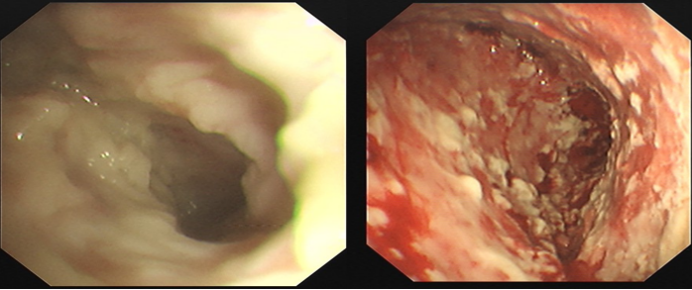

病例3:支气管扩张继发脓胸、脓毒症的患者,脓液多集中于叶间裂区域。经超声检查后,因胸腔内广泛粘连,缺乏适宜的进镜操作空间。基于此,考虑采用边进镜边探查脓腔的策略。进镜后,未发现脓腔,随后借助活检钳沿壁层胸膜进行钝性分离和探查,探及脓腔后扩大脓腔入口,进而进镜对脓腔进行清理(图5。术后第二天患者脓毒症状态迅速改善,术后1个月随访CT显示治疗效果理想。

图片

5  胸腔镜下所见